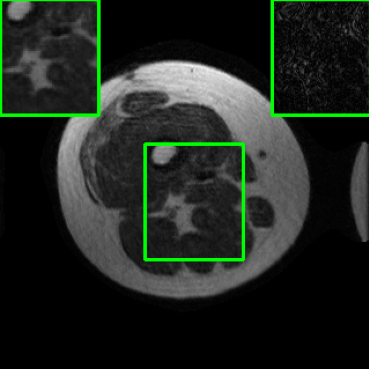

Performance on the Stanford FSE Dataset: We also performed image reconstructions with the Stanford multi-coil FSE dataset, which is a smaller dataset. We used same settings for the networks and training as in Section IV-A. Table III shows that LONDN-MRI significantly outperforms the globally learned MoDL network at both 4x and 8x acceleration. This indicates benefits for the proposed framework for smaller, more diverse datasets. Figs. 7 and 8 display visual comparisons that show the LONDN-MRI scheme recovering sharper features than the globally learned network.

| Ground Truth | Initial | Global | LONDN-MRI | LONDN-MRI | Oracle |

| (1 iteration) | (2 iterations) | ||||

![]() |

| PSNR = dB | PSNR = 19.41 dB | PSNR = 26.52 dB | PSNR = 27.76 dB | PSNR = 27.85 dB | PSNR = 27.92 dB |